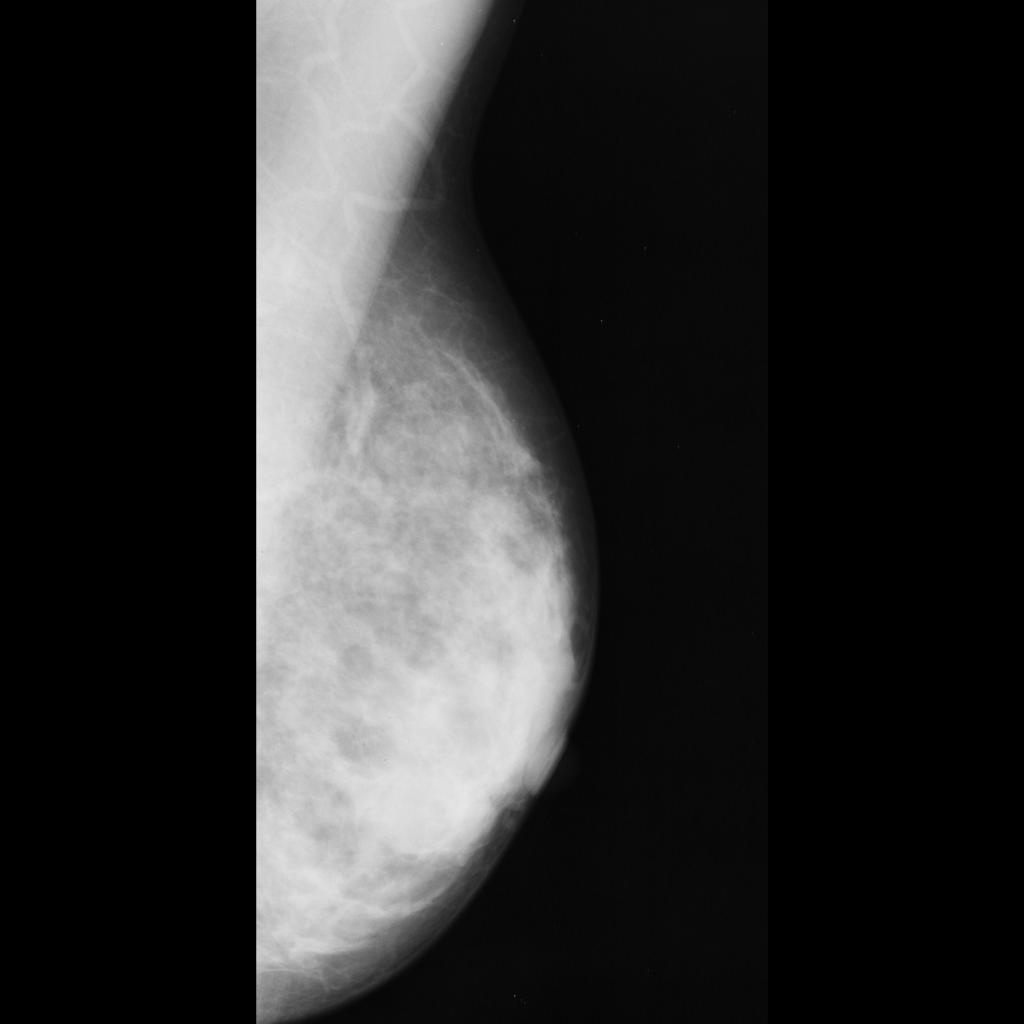

benign